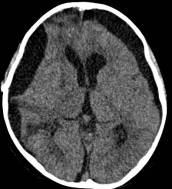

病例1:患儿男性,9岁。因反复出现意识丧失、视力下降半年收入院。入院后CT及 MRI显示颅内有形态不规则、“超大型”的颅咽管瘤,最大径约10厘米,见图1、图2。

图2.术前MRI

白色箭头指示肿瘤下极达枕大孔区